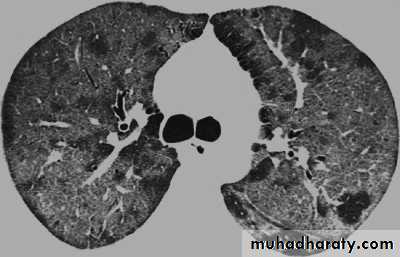

ParasiticPneumocystis jirovecii pneumonia (PJP). the old name is P.carinii pneomonia (PCP)

Pneumocystis jirovecii